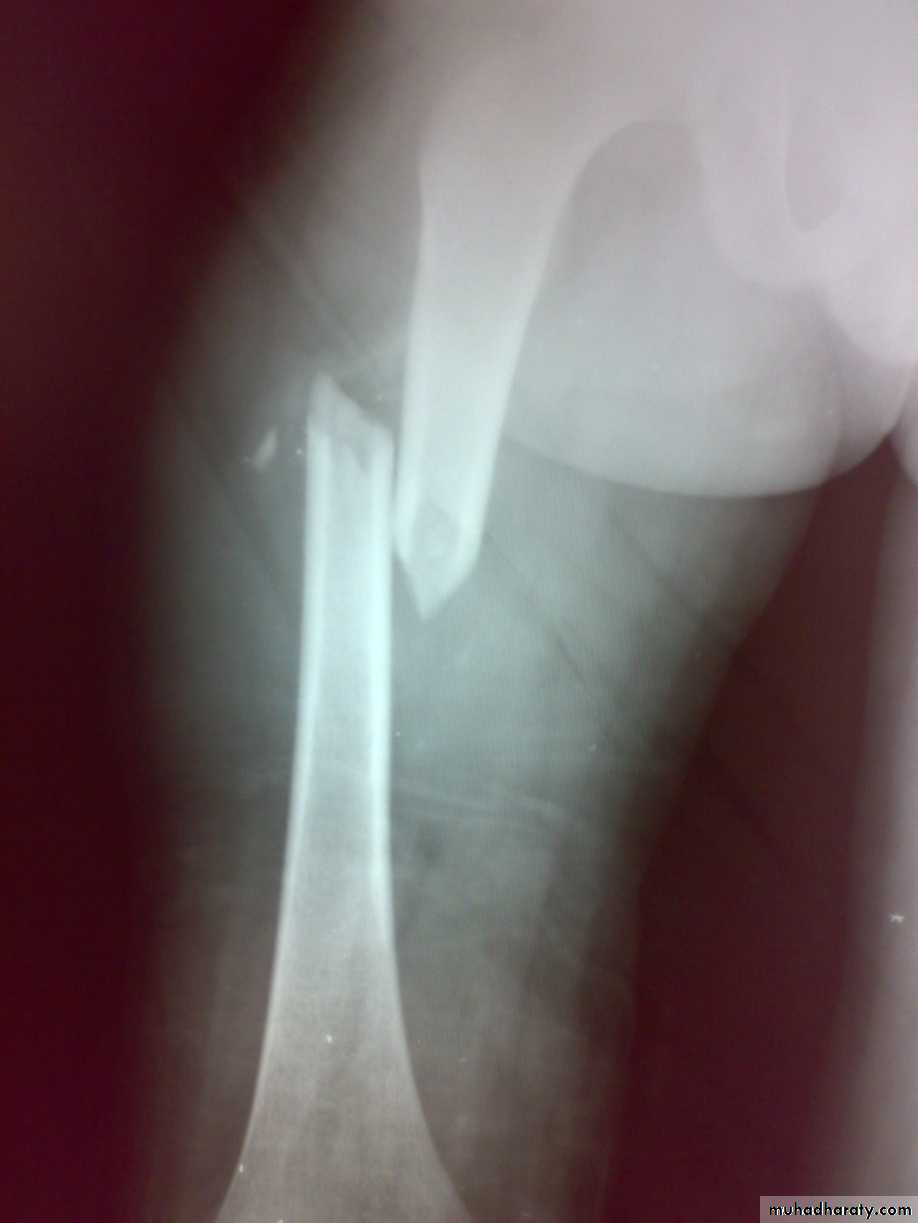

Slide 14. 20 Years old man presented following car accident.1- What is the diagnosis . what is the type of displacement?2- what is the best treatment